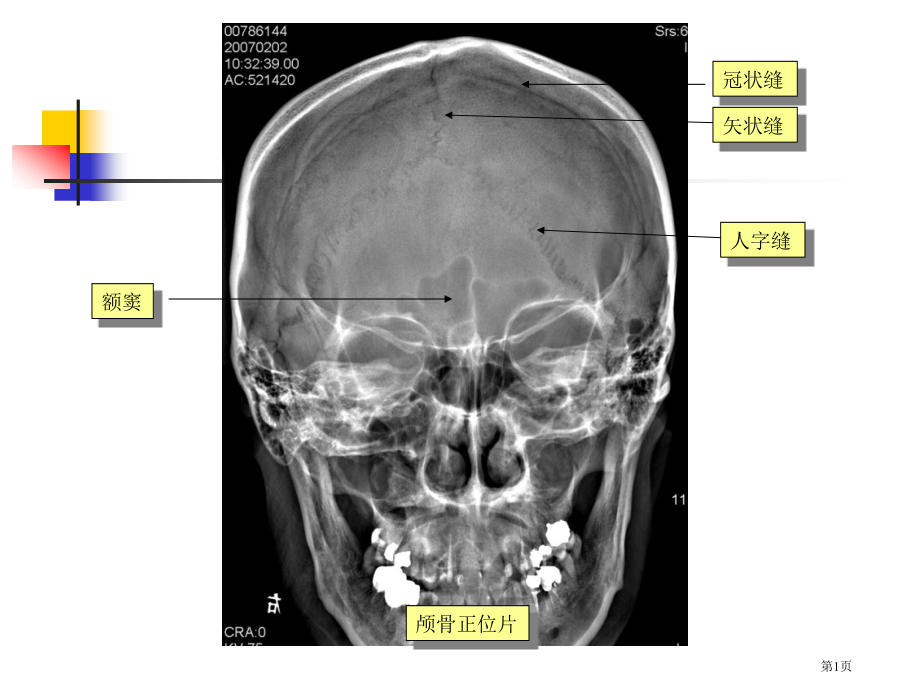

,单击此处编辑母版标题样式,单击此处编辑母版文本样式,第二级,第三级,第四级,第五级,*,矢状缝,人字缝,冠状缝,额窦,颅骨正位片,第1页,额骨,顶骨,枕骨,人字缝,蝶鞍,乳突气房,冠状缝,血管压迹,颅骨侧位片,第2页,眼动脉,大脑前动脉,大脑中动脉,颈内脉脉,后交通动脉,脉络丛前动脉,第3页,大脑前动脉,大脑中动脉,颈内脉脉,第4页,椎动脉,小脑下后动脉,基底动脉,小脑上动脉,大脑后动脉,小脑下前动脉,第5页,请指出主要脑动脉名称?,第6页,蝶窦,外耳道,小脑半球,延髓,颧骨,第7页,颞叶,垂体窝,四脑室,枕骨,桥小脑角池,鞍背,前床突,第8页,环池,脚间池,四叠体池,鞍上池,侧颞池,前纵裂池,第9页,侧裂池,侧脑室前角,侧脑室三角区,尾状核头部,胼胝体膝部,内囊后肢,丘脑,内囊前肢,豆状核,第10页,尾状核体部,侧脑室体部,额叶,枕叶,脉络丛,第11页,额叶,顶叶,放射冠,第12页,中枢神经系统MR影像解剖,1.颅底层面:从前向后包含额窦与筛窦、眼眶、蝶鞍、中颅窝、枕大孔与后颅窝等颅底结构。,第13页,中枢神经系统MR影像解剖,2.蝶鞍层面:此层面前可见额叶底部、眼眶顶壁,向后可见垂体窝、岩锥,并可见中颅窝和后颅窝脑组织。,第14页,中枢神经系统MR影像解剖,3.鞍上池层面:可见六角或五角星形水样信号鞍上池,其后为中脑,再后可见四脑室。,第15页,中枢神经系统MR影像解剖,4.三脑室前部层面:三脑室为双侧丘脑与下丘脑结构间窄带状缝隙,内含脑脊液,呈水样信号,此层面位置稍低,可见三脑室前部,于中脑后部可见四叠体池。,第16页,中枢神经系统MR影像解剖,5三脑室后部层面:可见三脑室后部及其后方松果体,此层面是观察三脑室与松果体区病变主要层面。三脑室前部可见两侧侧脑室前角。,6基底节层面:此层面主要结构是两侧内囊、基底节区和丘脑,该区是脑卒中好发部位。,第17页,中枢神经系统MR影像解剖,7侧脑室体部层面:可见双侧侧脑室体部,脑皮质、髓质和大脑纵裂,脑皮质包绕髓质区称为半卵圆中心。,第18页,中枢神经系统MR影像解剖,8脑室上层面:可见双侧额、顶叶脑沟、皮质、髓质和大脑纵裂。,第19页,第20页,中枢神经系统MR影像解剖,矢状面也是头颅MRI惯用检验层面,可显示中线结构形态及其毗邻关系,明确幕上和幕下结构。在正中矢状面上,可见中间胼胝体,由前向后分为膝部、体部和压部,脑干从上向下依次可识别中脑、脑桥和延髓。,第21页,中枢神经系统MR影像解剖,头颅冠状面惯用于鞍区病变显示,在垂体层面中线区由上向下可见大脑镰、胼胝体、两侧侧脑室、视交叉、垂体柄和垂体,下为蝶窦和后鼻孔。丘脑外侧可见内囊和豆状核等。,第22页,脊髓MR影像解剖,脊髓MRI惯用矢状面和横断面显示,在脊椎正中矢状面可见椎管内脊髓,最下端即脊髓圆锥,位于T12或L1水平,向下脊神经延续为终丝和马尾。周围可见在T1WI呈低信号、在T2WI中呈高信号脑脊液影像,与呈灰色信号脊髓对比清楚。但在MRI上,仍不能区分硬膜和蛛网膜结构。,第23页,脊髓MR影像解剖,横断面上则可于椎间孔层面显示向两侧走行神经根,神经根信号强度较低,在周围高信号脂肪组织衬托下显示十分清楚。,第24页,基本病变表现,高密度病灶,右基底节区血肿,钙化灶,第25页,基本病变表现,低密度病灶脑梗死,混合密度病灶脑挫裂伤,第26页,基本病变表现,均匀强化脑膜瘤,环形强化脓肿,第27页,基本病变表现,不均匀强化胶质瘤,第28页,基本病变表现,占位效应右侧侧脑室受压变形/移位,中线结构左移,第29页,基本病变表现,脑萎缩,脑积水,第30页,基本病变表现,左额顶骨粉碎性骨折,听神经瘤引发内听道扩大,第31页,基本病变表现,右侧基底节区肿块长T1长T2,第32页,基本病变表现,蛛网膜囊肿,长T1长T2信号,第33页,基本病变表现,水肿,长T1长T2信号,血肿,短T2信号,第34页,基本病变表现,脑梗死,长T2高信号,DWI呈显著高信号,第35页,左颞叶1级星形细胞瘤,第36页,T2WI,T1WI,T1WI,T1WI,右额叶1级星形细胞瘤,第37页,右侧小脑星形细胞瘤3级,T1WI-C+,T1WI-C+,第38页,右侧额叶少枝胶质瘤,条状钙化,钙化显示CT优于MRI,MRI钙化显示不清,第39页,脑梗死低密度灶呈楔形,边界清楚,与动脉供血区相一致,有脑回状强化,第40页,脑脓肿壁较光滑,厚薄均匀,普通无壁结节,第41页,成血管细胞瘤好发于小脑半球,壁结节小,显著强化,囊壁无强化。,显著强化壁结节,第42页,增强后肿块显著强化,等密度肿块,等密度肿块,颅骨内外肿块,增强CT,增强MRI,平扫CT,第43页,不经典囊实性脑膜瘤,右侧桥小脑角区脑膜瘤,第44页,束腰征,第45页,左侧骨性内听道扩大,增强MRI示左侧管内段 听神经瘤,双侧听神经瘤,第46页,鞍区囊性肿块伴蛋壳样钙化,第47页,脑转移瘤增强MRI,第48页,右侧额叶脑挫伤,双侧额叶脑挫裂伤,双侧额叶脑挫裂伤,第49页,硬膜外血肿,第50页,右侧急性硬膜下血肿,双侧慢性硬膜下血肿增强CT表现,第51页,右侧慢性硬膜下血肿CT表现,右侧慢性硬膜下血肿MRI表现,第52页,蛛网膜下腔出血,第53页,急性脑出血,第54页,左侧基底节区血肿残腔,脑出血吸收期改变,第55页,中脑恶急性脑出血,T1WI及T2WI均呈高信号,第56页,动脉致密征,第57页,岛带征,第58页,缺血性脑梗死,出血性脑梗死,第59页,腔隙性脑梗死,缺血性脑梗死,MRA示左侧大脑中动脉分支显著降低,右侧基底节区脑梗死CT表现,第60页,大脑前动脉合并出血,CTA,DSA,第61页,鞍上动脉瘤,第62页,大脑前动脉动脉瘤,第63页,右侧大脑中动脉巨大动脉瘤,部分血栓形成动脉瘤,第64页,右侧大脑中动脉区动静脉畸形,CTA,第65页,结核性脑膜炎,第66页,结核性脑膜炎及结核球,第67页,脑脓肿,第68页,多发性硬化,第69页,胼胝体缺如,胼胝体发育不全,正常胼胝体,第70页,Chiari畸形,Chiari畸形伴脊髓空洞症术后,第71页,神经鞘瘤,室管膜瘤位脊髓空洞症,第72页,外伤性脊髓损伤(三个不一样病例),第73页,脊膜膨出,第74页,Chiari畸形合并脊髓空洞症,第75页,颈段脊髓血管畸形,第76页,胸段脊髓血管畸形CTA,第77页,更多资源xiti123.taobao,高一语文,高一英语,高一数学,高一物理,高一化学,高一政治,高一历史,高一地理,高一生物,第78页,